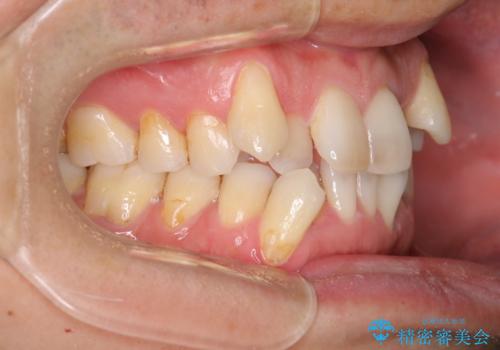

- 治療計画

叢生量が大きいため、上下顎両側4番を抜歯しました。矯正治療による歯肉退縮の著しい悪化もなく、主訴であるガタつきも改善できました。